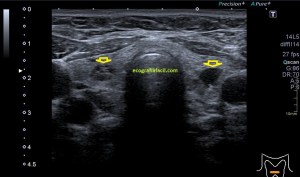

En la imagen 3 ves una imagen de un lipoma, mide 7 cms, la huella de la sonda mide 5cms, la «panoramic view» posee una regla centimetrada que sigue el contorno de la imagen, justo en la profundidad de la misma y lo marca la flecha amarilla. La profundidad la marca la flecha roja y la flecha blanca marca el rango centimetral de los 5cms, fíjate que la línea blanca es ligeramente mayor cada 5 cms. Sirve de referencia, como en la imagen 4 donde ves una colección en el glúteo de más de 10 cms.